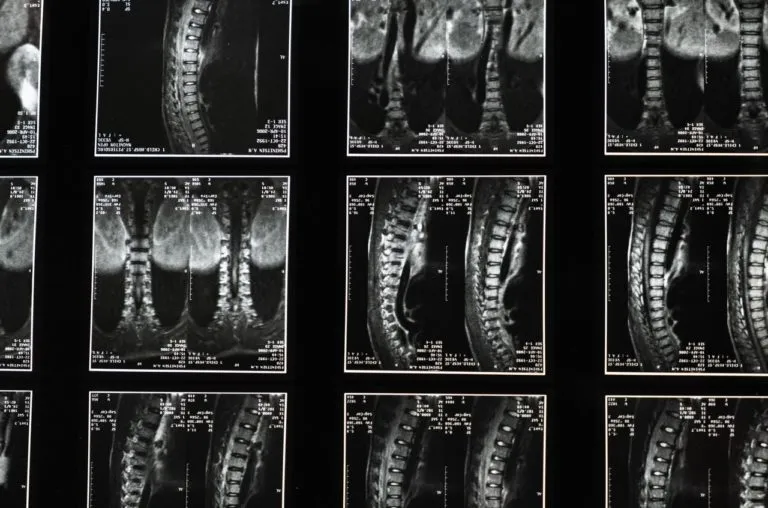

- Rezonans magnetyczny (MRI): Uważany za złoty standard w diagnostyce schorzeń kręgosłupa. Pozwala na bardzo dokładne zobrazowanie tkanek miękkich, takich jak krążki międzykręgowe (dyski), rdzeń kręgowy, nerwy. Jest niezastąpiony w wykrywaniu przepuklin dysków, stanów zapalnych czy zmian nowotworowych.

- Tomografia komputerowa (TK): Bardzo dokładne badanie, szczególnie przydatne do oceny struktur kostnych, na przykład po urazach. Pozwala na uzyskanie przekrojowych obrazów kręgosłupa.